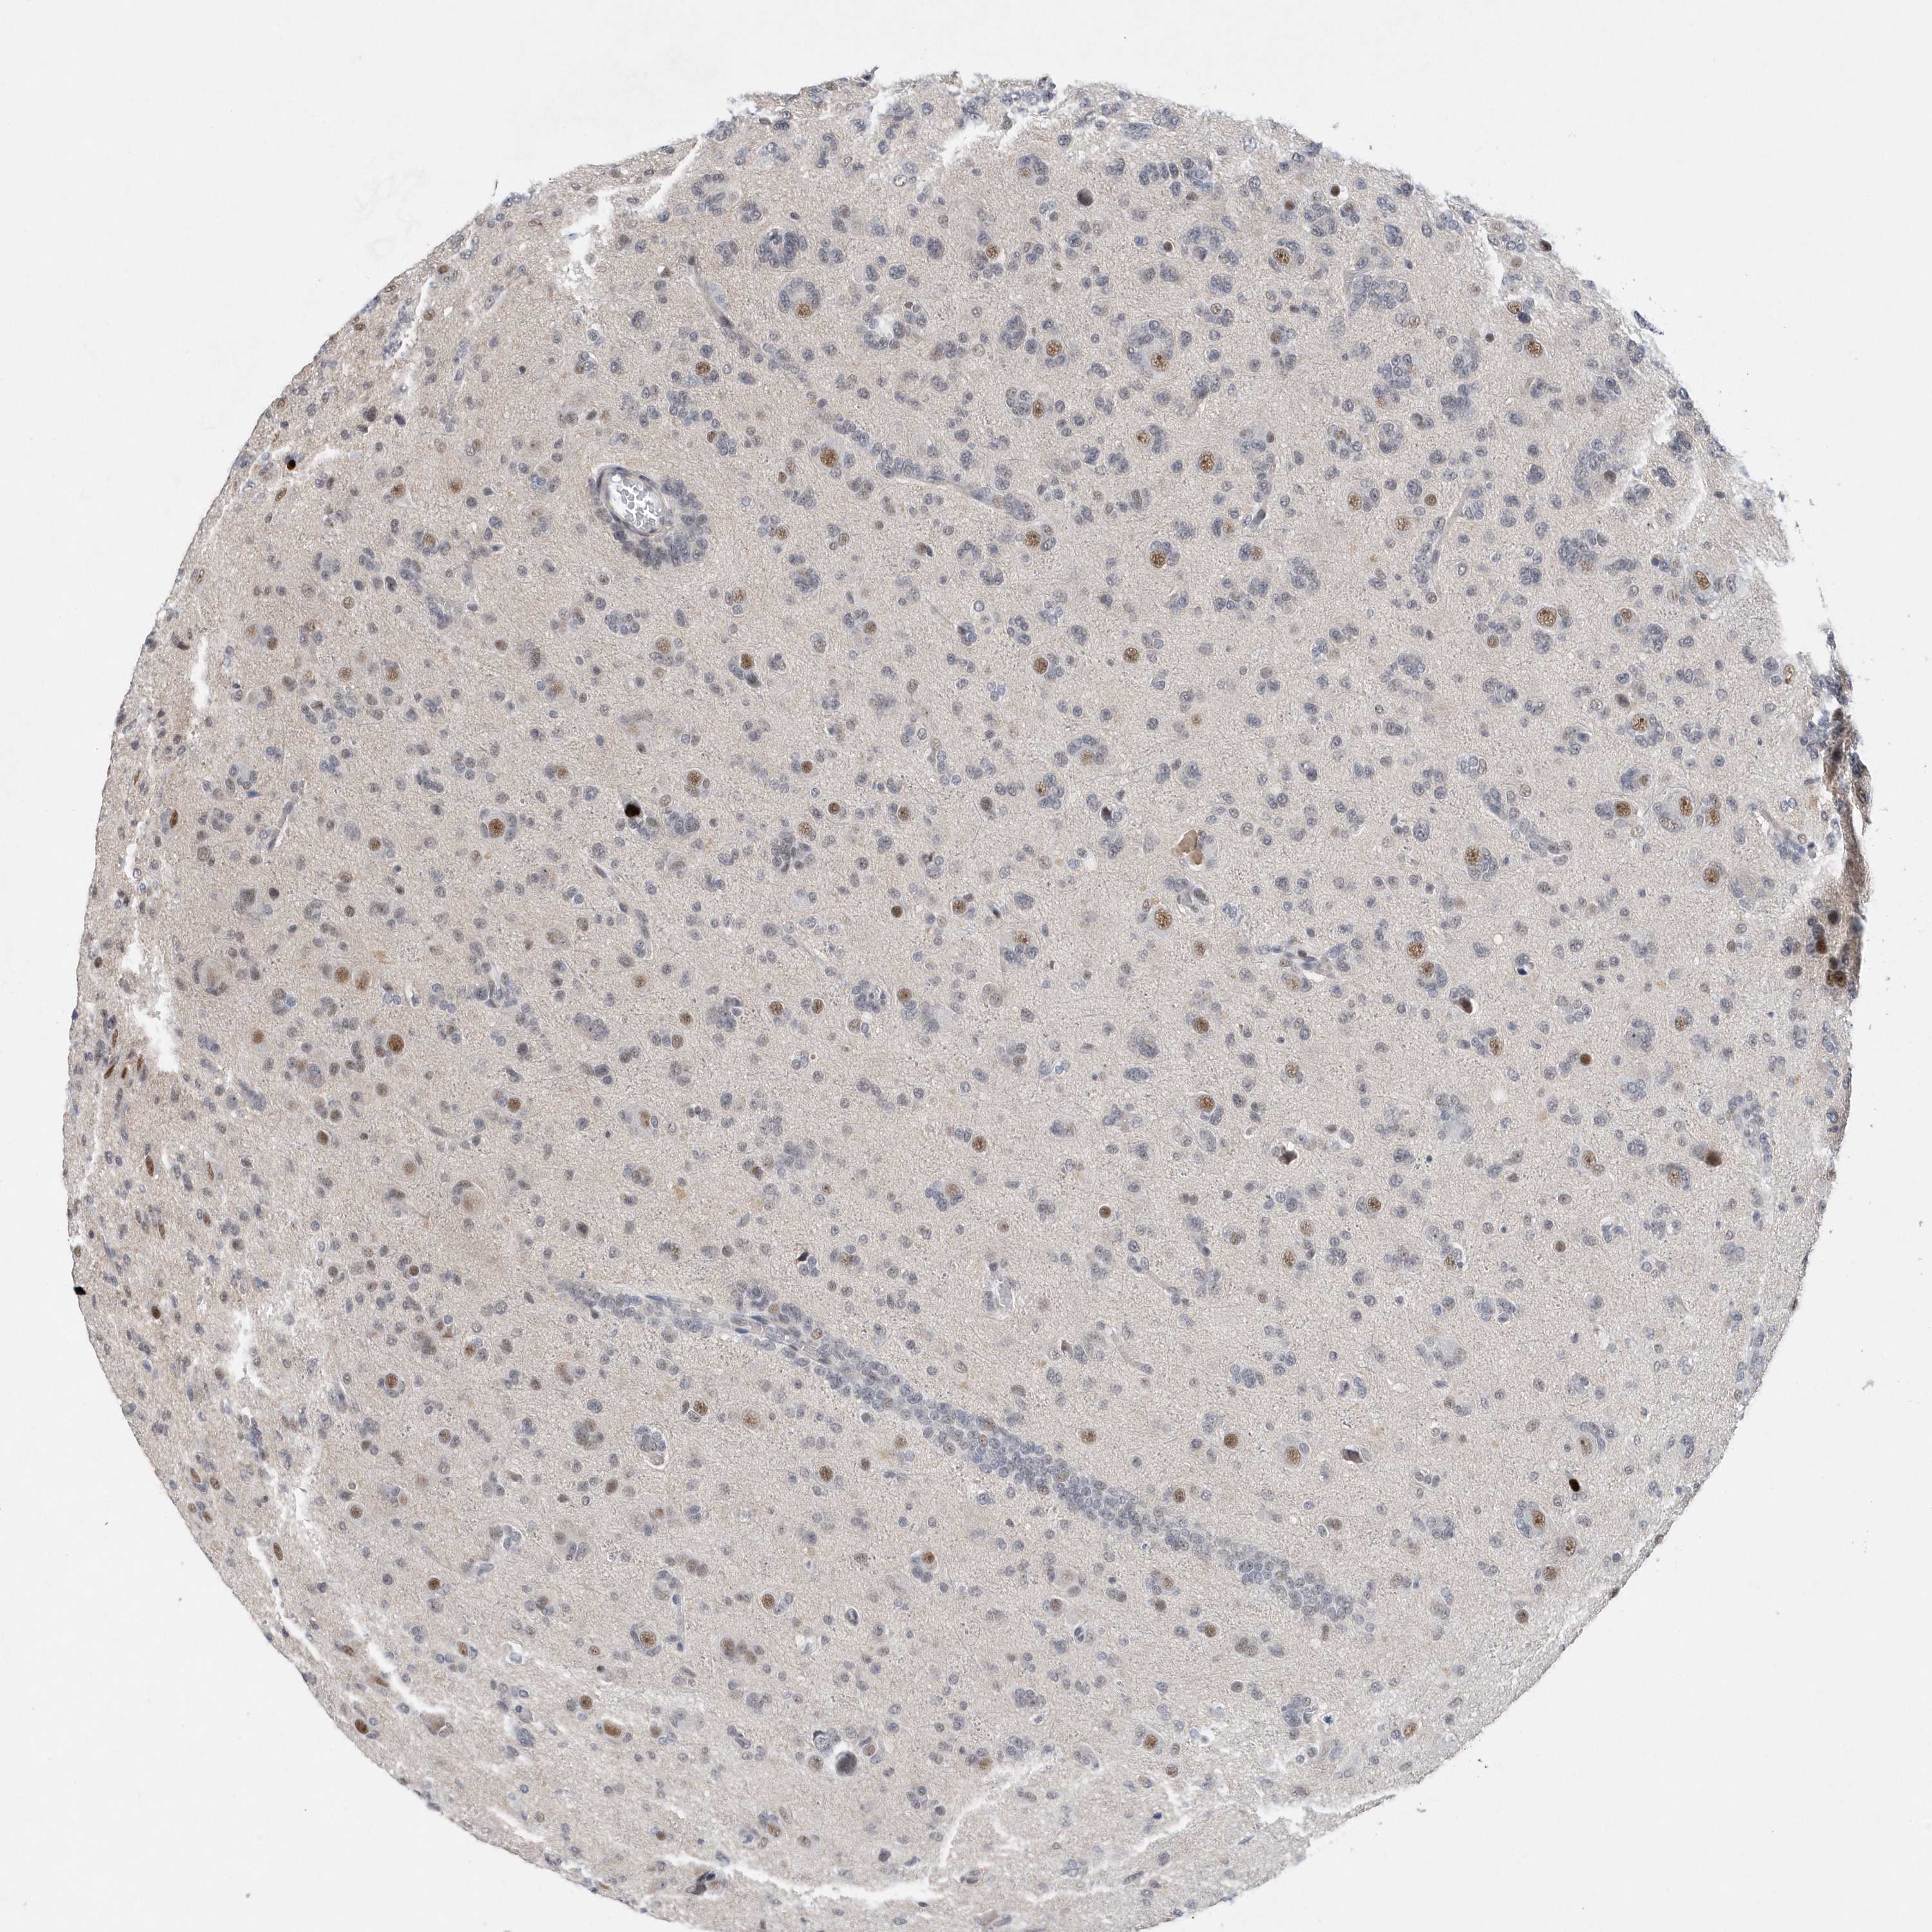

GLIOMA - Protein expressioni

A mouse-over function shows sample information and annotation data. Click on an image to view it in a full screen mode. Samples can be filtered based on level of antibody staining by selecting one or several of the following categories: high, medium, low and not detected. The assay and annotation is described here.

Note that samples used for immunohistochemistry by the Human Protein Atlas do not correspond to samples in the TCGA dataset.

Antibody stainingi

Antibody staining in the annotated cell types in the current human tissue is reported as not detected, low, medium, or high, based on conventional immunohistochemistry profiling in selected tissues. This score is based on the combination of the staining intensity and fraction of stained cells.

Each image is clickable and will lead to virtual microscopy that enables deeper exploration of all samples and also displays staining intensity scores, fraction scores and subcellular localization as well as patient and tissue information for each sample.

Antibody HPA037578

Staining

High

Medium

Low

Not detected

Intensity

Strong

Moderate

Weak

Negative

Quantity

>75%

75%-25%

<25%

None

Location

Nuclear

Cytoplasmic/membranous

Cytoplasmic/membranous,nuclear

Glioma, malignant, High grade

Glioma, malignant, Low grade

Glioblastoma, NOS